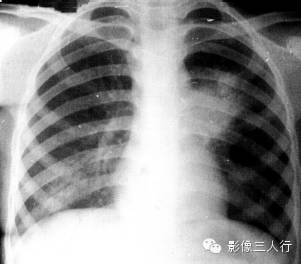

报告示范:左肺上野见边缘模糊的片状阴影,左肺门增大。胸廓对称,气管居中。心脏形态、大小、位置正常。双侧膈肌光滑,肋膈角锐利(图1)。

图1原发综合征